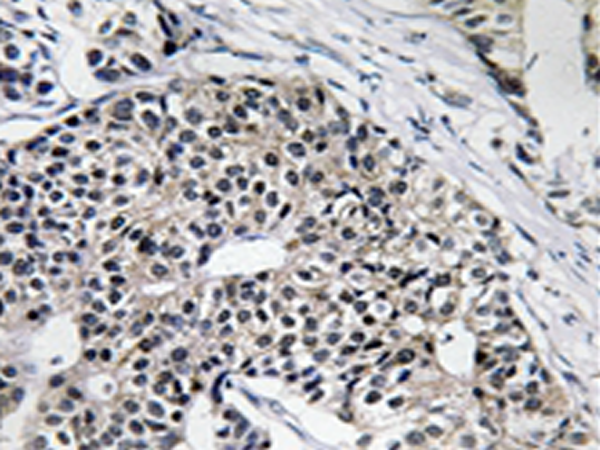

IHC positive control: |

Human breast carcinoma tissue |

IHC Recommend dilution: |

50-100 |